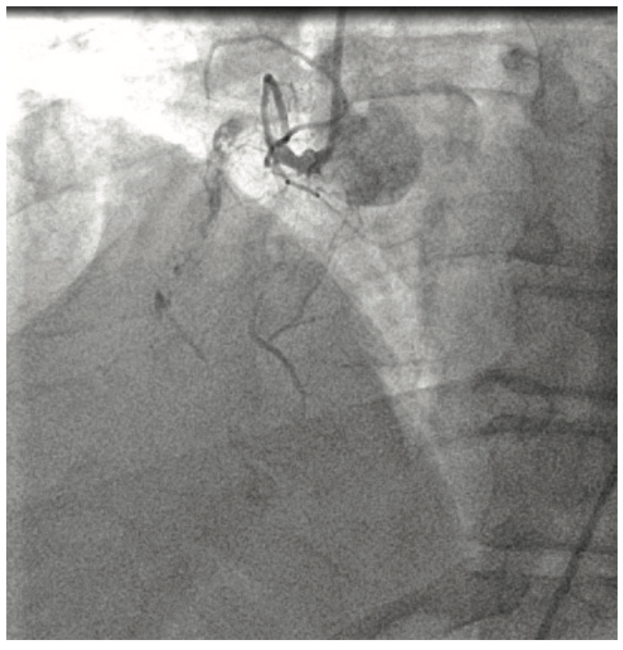

Percutaneous coronary intervention (PCI) of chronic coronary total occlusion (CTO) has been considered the final frontier in percutaneous intervention. There have been vast improvements in the initial success and safety of the procedure, as well as a better understanding of appropriateness and benefits. Advances in technology and technique allow for increased utilization of PCI in cases of chronic CTO, with benefits regarding symptoms and quality of life. PCI for chronic CTO allows for correction of ischemia and complete revascularization, avoiding the need for traditional coronary bypass grafting while offering increased survival benefits.